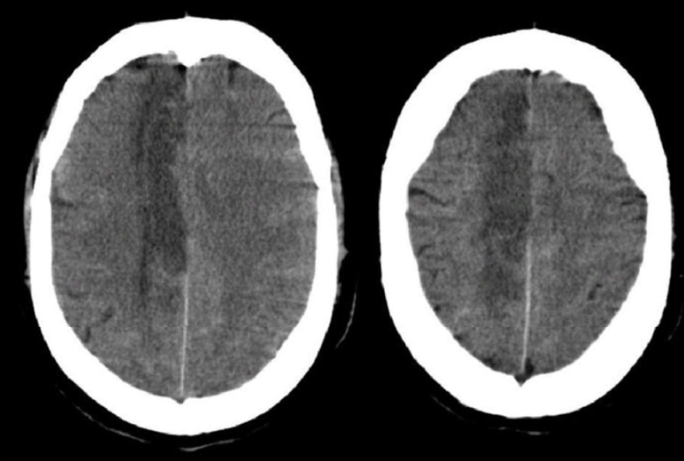

pt has contralateral hemiplegia, hemisensory loss, and homonymous hemianopia (b/l symmetric loss of vision in half the visual fields) w eyes deviated to side of lesion

MCA infarct

MCA infarct leads to a large risk for

hemispheric swelling, stupor, coma, confusion